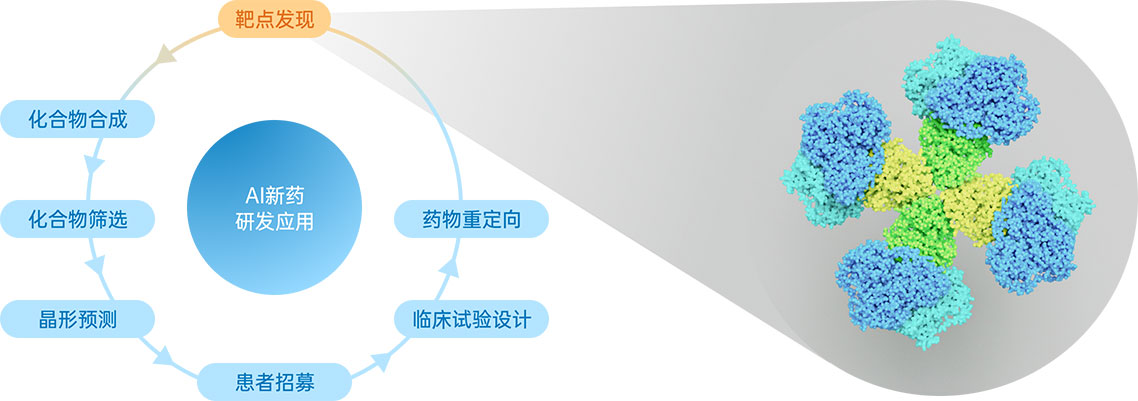

人工(gōng)智能(néng)的发展正在全面推动我们的生活,同样的,对新(xīn)药研发过程也起到积极推动的作(zuò)用(yòng)。 华深智药是一家致力于设计精(jīng)确靶向抗原表位新(xīn)型抗體(tǐ)的药品研发企业,利用(yòng)人工(gōng)智能(néng)技(jì )术Artificial Intelligence Technology与大型药企联合研发新(xīn)药。而相较于传统药品研发流程,人工(gōng)智能(néng)的介入将提高药物(wù)开发过程的效率并降低成本。

我们寻找能(néng)够清晰向用(yòng)户传达“华深智药致力于做什么”的视觉介质(zhì),因此深入分(fēn)析行业属性及挖掘华深智药的独特之处。华深智药致力于设计精(jīng)确靶向抗原表位新(xīn)型抗體(tǐ),而该环节——靶点发现处于AI研发新(xīn)药的药物(wù)发现阶段,因此我们决定选择可(kě)视化动态呈现企业主要业務(wù),帮助用(yòng)户快速了解华深智药。